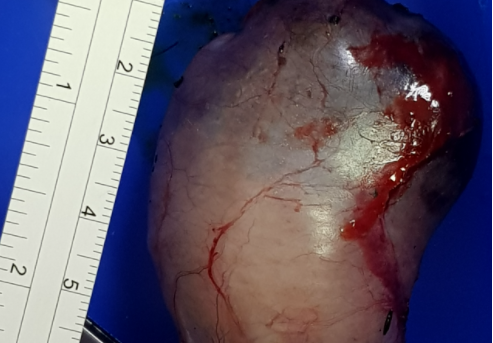

• 子宮蓄膿的狗狗 股骨頭脫位 尿道結石 胃扭轉(GDV) 急性腎損傷

子宮蓄膿的狗狗 股骨頭脫位 尿道結石 胃扭轉(GDV) 急性腎損傷